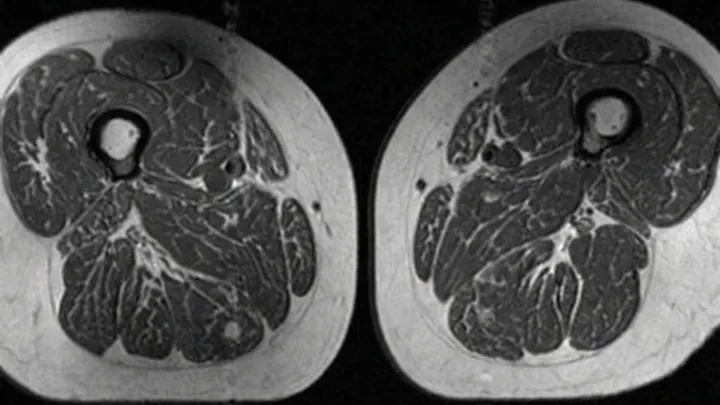

Researchers used imaging to quantify intramuscular adipose tissue and found that higher intake of ultraprocessed foods tracked with greater fat infiltration, even when total body weight was similar. That shift in body composition can erode lean mass, depress basal metabolic rate and impair muscle contraction, making falls more likely and fractures more severe when they occur.